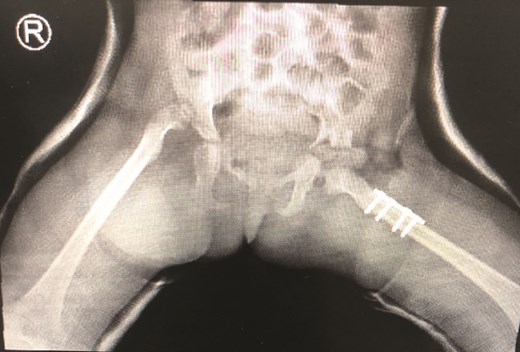

The patient underwent left hip open reduction, pelvic osteotomy, femoral shortening and hip spica followed by open reduction, pelvic osteotomy, femoral shortening and hip spica for the contralateral side six months later (Figs 2–4), the intervention was similar to regular DDH cases, no differences were noted during the surgical management. The patient was followed up closely in the clinic, and she had the implants removed after one year (Fig. 5). The patient recovered fully without any apparent postoperative complications. She was followed up in the clinic for 3 years, and she recovered fully without any complications.

Second stage correction of DDH after 6 months from the first stage procedure.